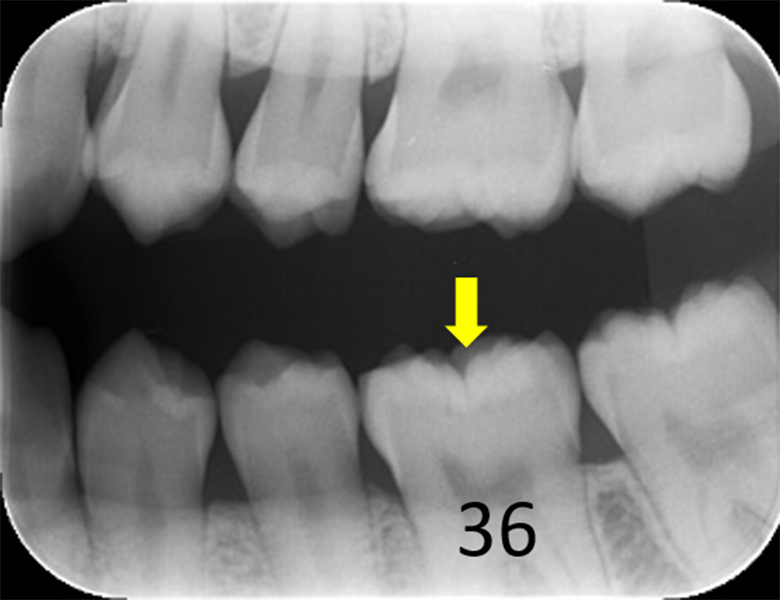

症例② 下顎大臼歯 小窩や裂溝の虫歯 20歳女性

初診時口腔内写真 |

![]() 初診時レントゲン写真 |

症例①②

主訴 |

正しい口腔ケアを知り、健康的になりたい。 |

診断 |

上下大臼歯の初期虫歯 |

治療 |

経過観察 |

期間 |

経過観察中 |

費用 |

0円 |

治療リスク |

虫歯進行の可能性 |